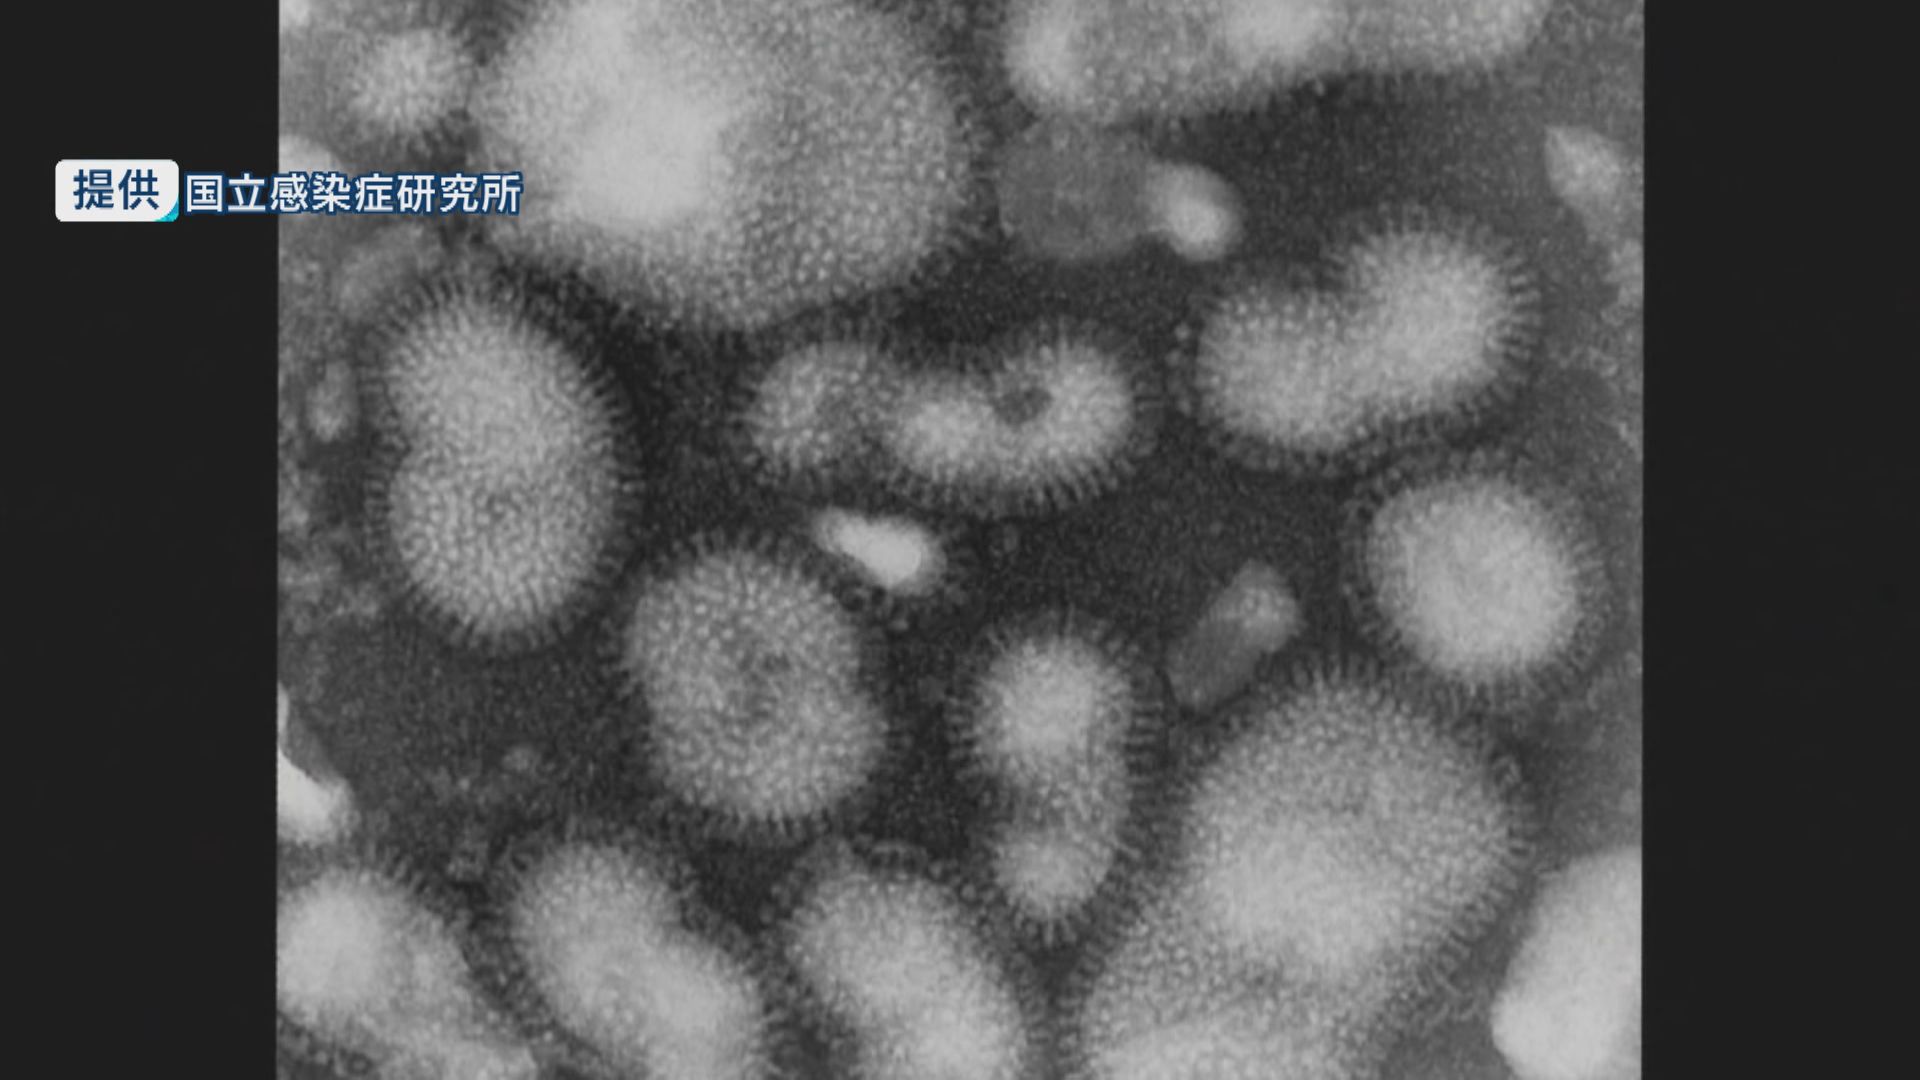

インフルエンザ流行警報が18週ぶりに解除

長崎市で麻しん(はしか)患者発生 20代女性3月21日から発熱・発疹も「非常に強く空気感染」のため注意呼びかけ

インフルエンザ感染者が6週間ぶり増加 前週比で18人増の639人 10歳未満が全体の約半数、10代が3割以上

インフルエンザ感染者は5週連続減少し621人 前週比で238人減ながら警報レベル 基本的な感染予防呼びかけ